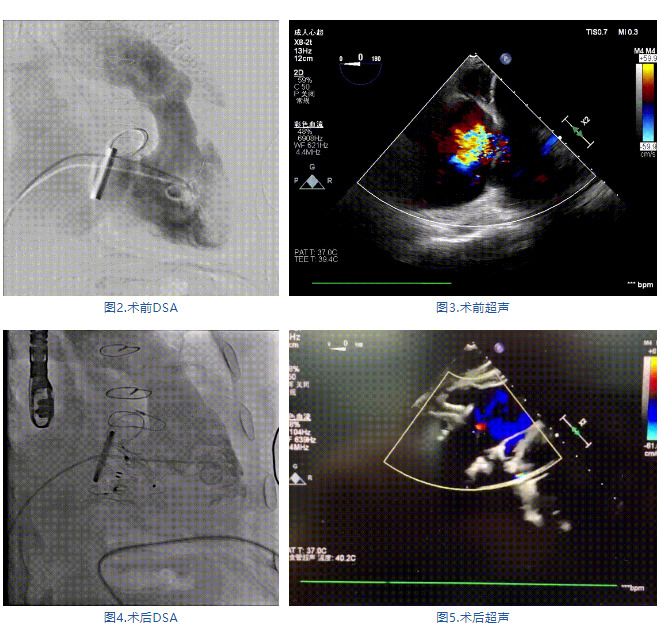

手術(shù)在全麻狀態(tài)下進行,郭惠明教授團隊采用經(jīng)右側(cè)頸靜脈入路的方式送入輸送器進入體內(nèi),并在TEE和DSA的指引下進行。在輸送器進入右室后釋放室間隔錨定裝置,旋轉(zhuǎn)輸送器,使得錨定裝置對準(zhǔn)室間隔面;而后釋放前瓣夾持件,確定夾持件位于右室側(cè)釋放LuX-Valve Plus人工瓣膜盤片,再使用DSA和超聲確認(rèn)盤片是否位于右房側(cè),同時調(diào)整瓣膜的同軸性。緊接著在DSA和超聲的監(jiān)視下調(diào)整室間隔錨定件貼合室間隔,釋放室間隔錨定裝置。再次確認(rèn)瓣膜的穩(wěn)定性和同軸性后,將輸送器撤出體內(nèi),最終完成LuX-Valve Plus人工瓣膜植入(圖2-5),手術(shù)獲得圓滿成功。患者在手術(shù)室即刻拔除氣管插管,術(shù)后超聲提示LuX-Valve Plus人工三尖瓣瓣膜同軸性良好,瓣架固定牢靠,無反流和瓣周漏。